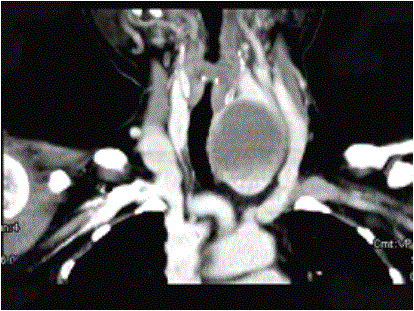

问题 女,56岁,发现颈部肿块30天,颈部肿大,无红肿热痛,无呼吸困难,无吞咽困难,无心悸胸闷烦躁史。近1个月来因肿大不适而来就诊。发病来饮食睡眠正常,体重无下降。如图所示该患者最可能诊断为()

选项 A.甲状舌管囊肿 B.甲状腺乳头状癌 C.甲状腺原发淋巴瘤 D.甲状腺腺瘤 E.甲状腺脓肿

答案 D